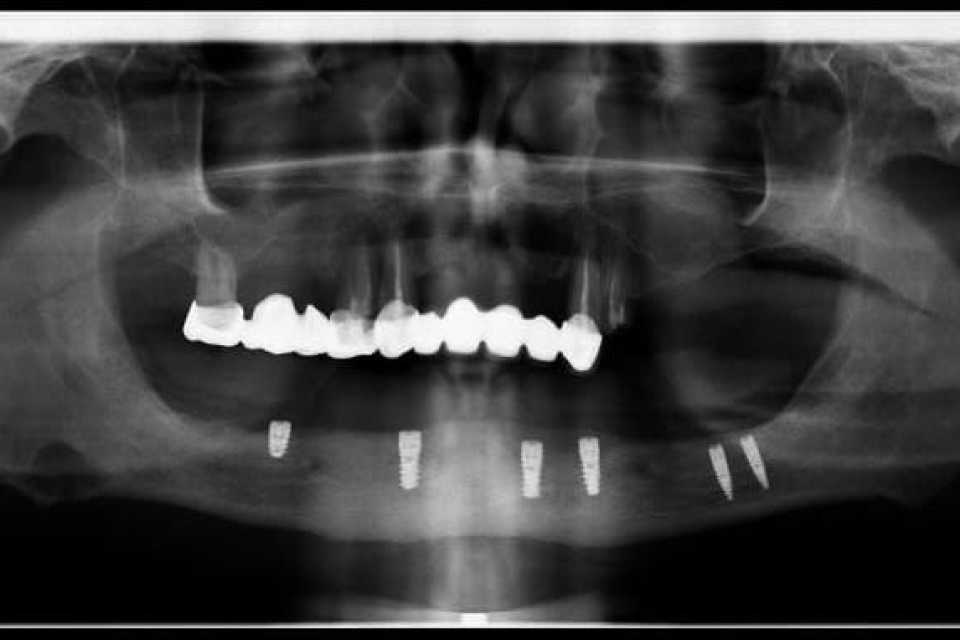

Pacient în vârstă de 45 de ani, vechi purtator de proteza totală inferioara s a prezentat cu dorința de a efectua o lucrare pe implanturi fixa.

Cazul a fost unul foarte dificil prin prisma resorbtiei osoase în zonele laterale mandibulare și ale patologiilor asociate ale pacientului, prohibitive pentru adiții osoase.

Astfel, am optat, impreuna cu pacientul, pentru 6 implanturi Straumann BLX Roxolid, inserate lateral de nervul alveolar inferior, metodă care ne-a ajutat sa evitam procedura de aditie osoasă, pe care am realizat o lucrare fixa insurubabila din Zirconiu.